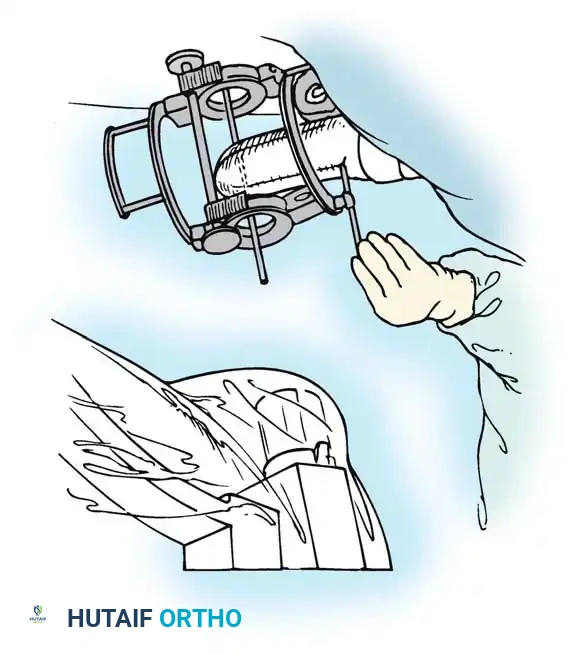

Fig. 58-26 Speed technique of open reduction. A, Incision and ulnar nerve isolation. B, Triceps aponeurosis reflected distally; subperiosteal stripping of muscles. C, Lateral view showing extent of mobilization. D, V-Y closure.

Subperiosteally free all muscle attachments from the distal humerus, both anteriorly and posteriorly.

Aggressive subperiosteal elevation is required to mobilize the distal humerus completely.

Release the attachments of the joint capsule and collateral ligaments around the humeral condyles. Mobilizing the tissues around the medial condyle and anterior humerus can be exceptionally difficult due to scarring, but complete mobilization of the distal humerus is non-negotiable for reduction.

Triceps Flap and Subperiosteal Stripping

Beginning proximally, use sharp dissection to reflect the aponeurosis of the triceps distally, forming a robust tongue-like flap of tissue that remains attached to the olecranon.

Starting 7.5 cm proximal to the joint, make a midline incision through the underlying muscle fibers of the triceps down to the olecranon. Curve this deep incision around the lateral edge of the olecranon.